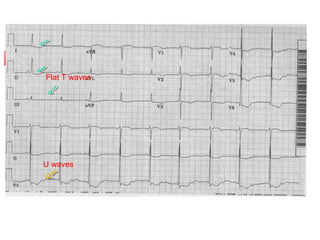

   Early changes

Flattening or inversion of T waves

Prominent U waves

ST segment depression

Prolonged QT interval

Flattening of T waves

Flat T waves

U waves